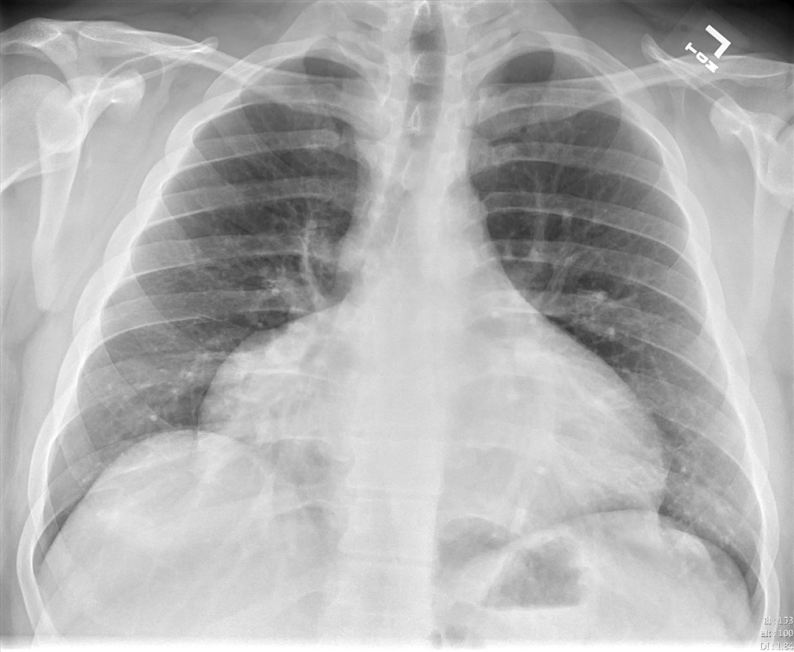

AP projection is obtained with the patient in bed and lying flat or partly upright. It is usually reserved for non-ambulatory patients. AP projections have the disadvantage of making the heart an mediastinum appear more prominent as well as usually resulting in shallower inspiration which can limit evaluation of the lung bases. A lateral projection is not obtained with a AP projection, thereby limiting the view of the chest further.

AP Projection – Widened Mediastinum and Less Inspiratory Effort

It is therefore preferable to order a PA/lateral CXR over an AP view when possible.